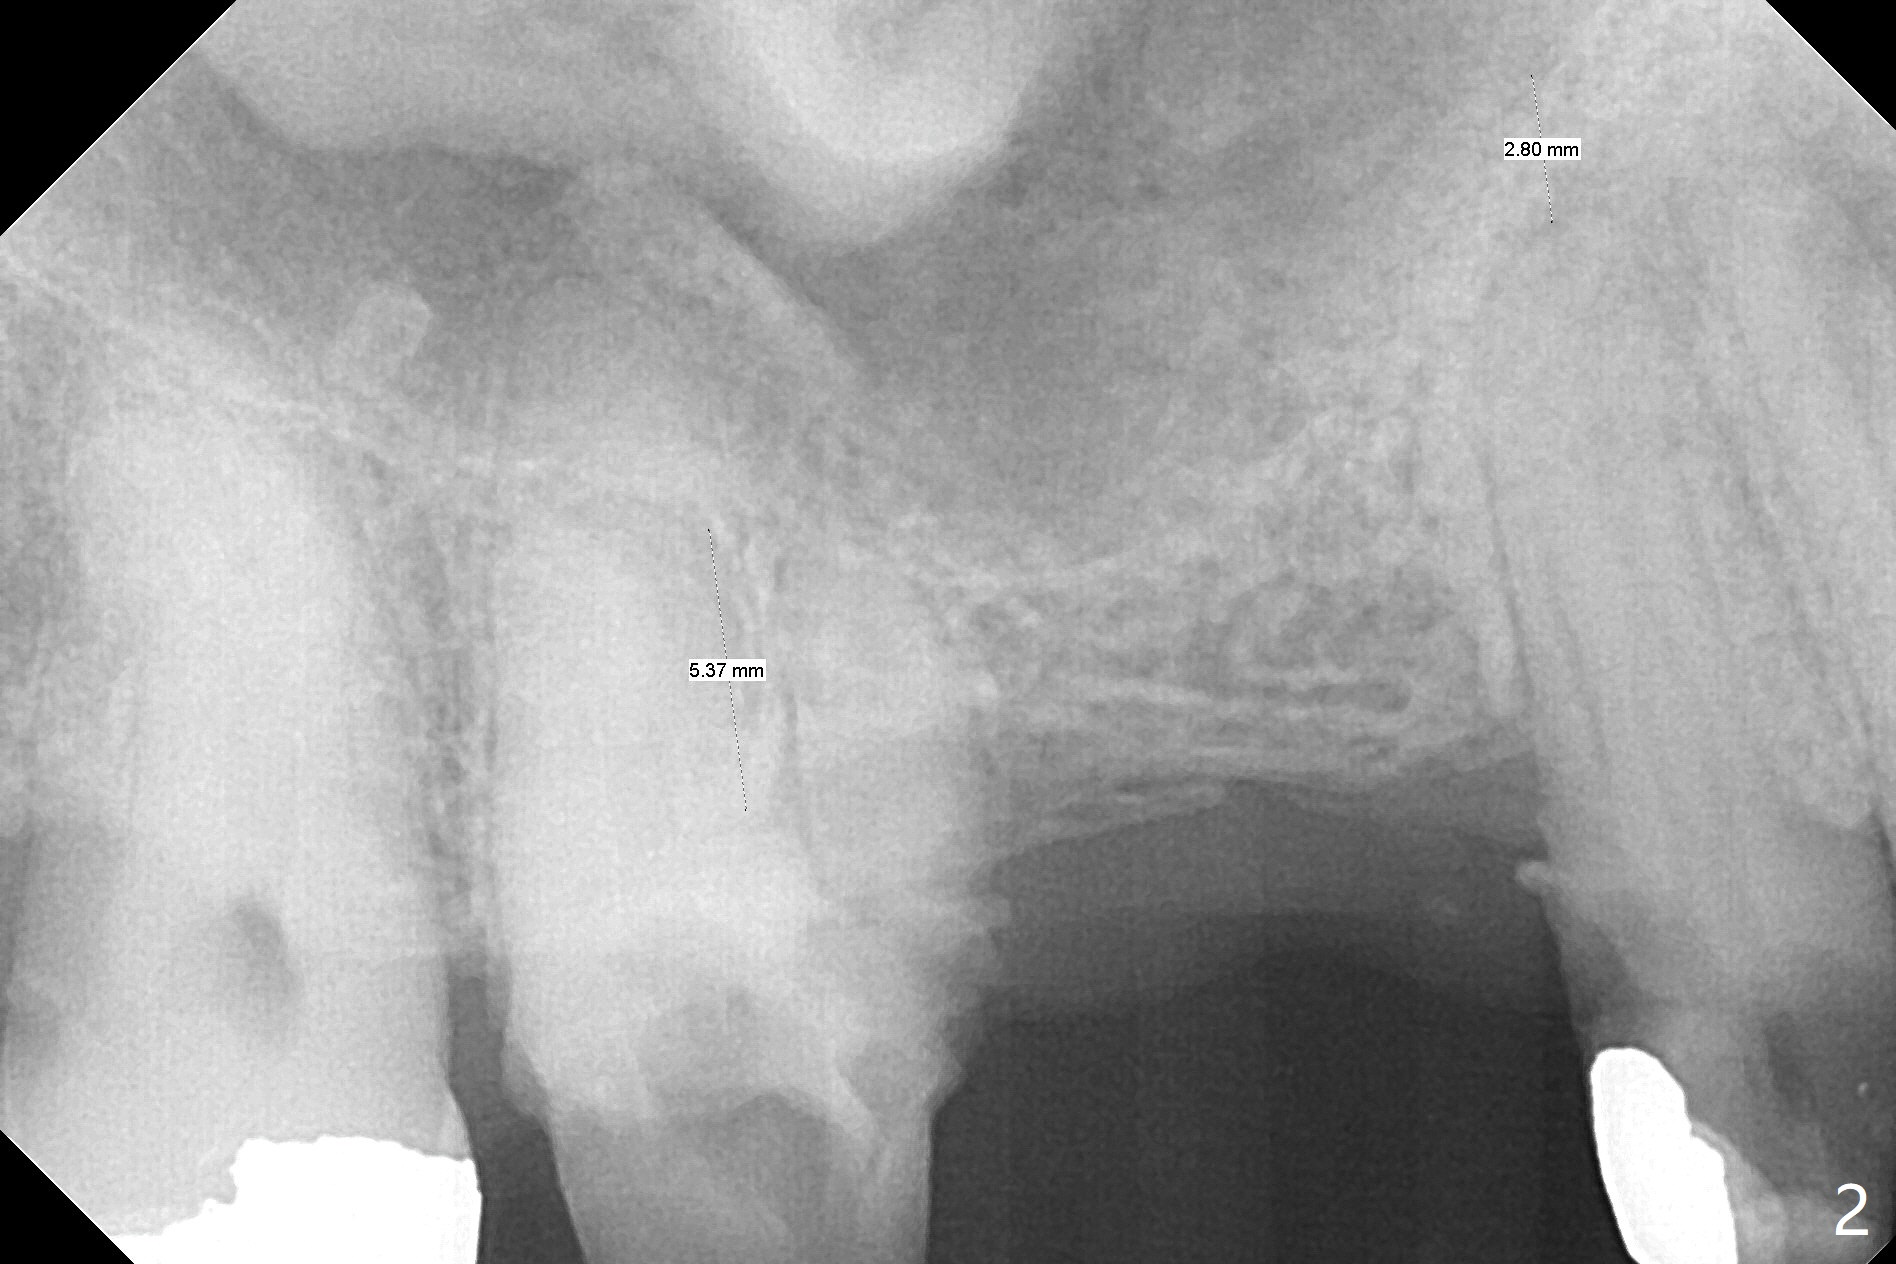

A 64-year-old man requests implant restoration after the upper FPD dislodges (Fig.1). The measurement of the septal height at #2 by PA (Fig.2) is not as precise as CBCT (Fig.11, taken 4 years earlier). There appears to be 2.8 mm bone apical to the tooth #4 (Fig.2); in contrast, the bone is more or less buccal and palatal to the root apex shown by CT (Fig.5). Furthermore CT more clearly shows apical lesions of the tooth #5 (Fig.3,4) than PA (Fig.2). In addition to pulpal test, RCT should be done for #5 prior to implant placement at #4.